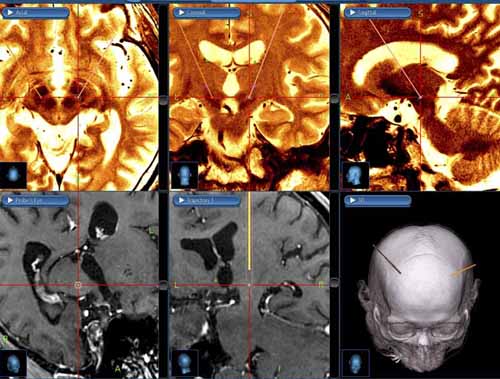

DBSの手術手技について、手術前には必ず精度管理(写真1)と術前プランニング(写真2)を行い、ナビゲーションと術中の微小電極記録(写真3,写真4)をもとにして、5mmサイズの視床下核を同定します。そして電極針の位置がずれないように術中透視でモニターしながら、DBSリード電極を留置します(写真6)。通常は、局所麻酔でリード電極留置術を行いますが、術中せん妄が予想される場合には全身麻酔で行います。

手術前に電極とターゲットのズレを確認している。

手術前に造影MRIを撮影して、血管構造をチェックして、穿刺ルートを同定している。